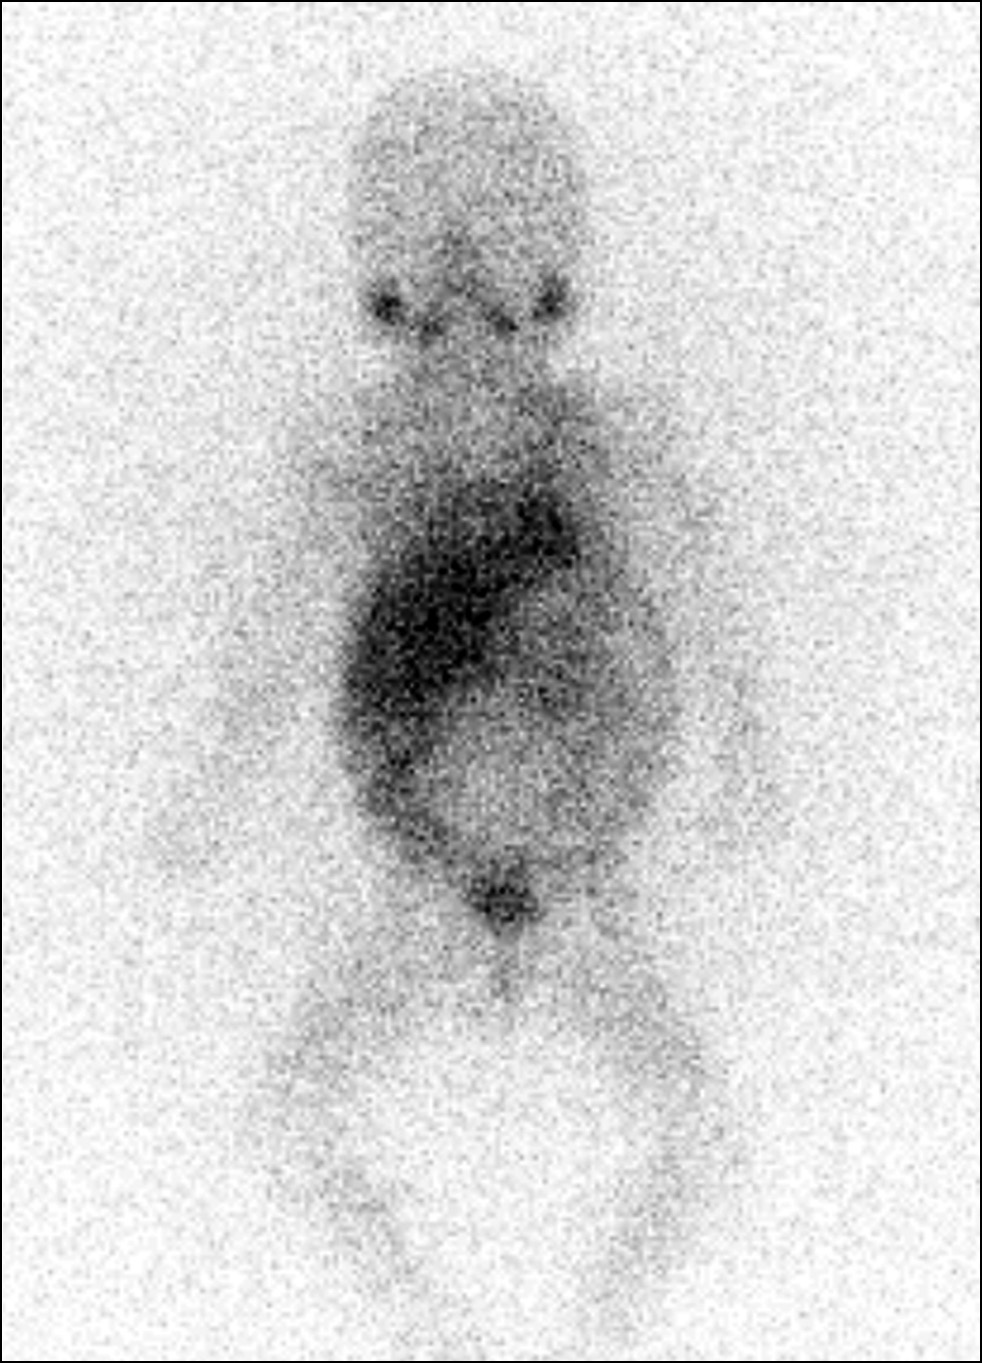

October 30, 2020: A metaiodobenzylguanidine scintigraphy demonstrated no reliable signs of radiopharmaceutical uptake (Fig. 3).

Fig. 3. Metaiodobenzylguanidine scintigraphy dated October 30, 2020. There was no indication of radiopharmaceutical uptake.